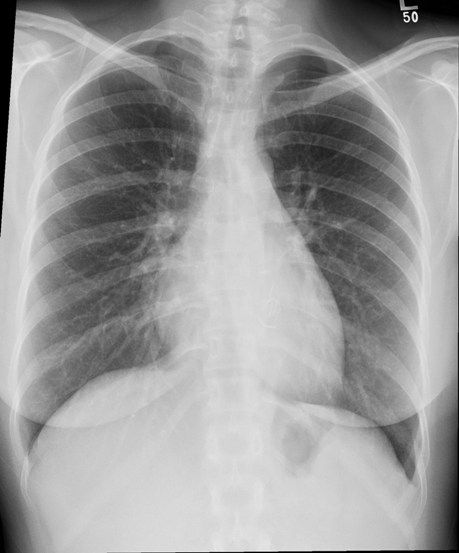

A chest X-ray is most commonly used to detect abnormalities in the lungs but can also detect abnormalities in the heart aorta and the bones of the thoracic area. Investigation with ultrasound andor CT is required for assessment of a suspected abdominal mass. Most of the worst lung conditions are detected using an X-ray.

Fees tend to be higher on the coasts and in the big cities lower in more rural areas. Chest X-rays can detect some lung and heart abnormalities like tumors as well as rib fractures. It depends on the size and location of the mass.